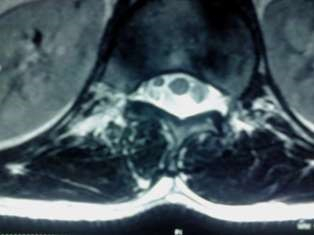

Spinal Tumors

A spinal tumor is a growth that develops within your spinal canal or within the bones of your spine. A spinal cord tumor, also called an intradural tumor, is a spinal tumor that that begins within the spinal cord or the covering.